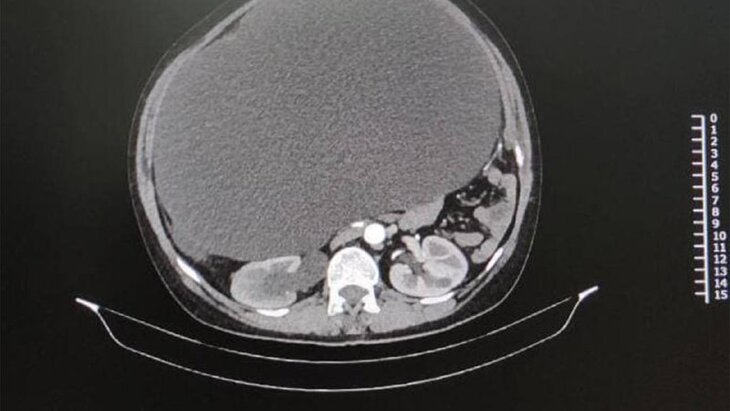

В Подмосковье врачи Ступинской больницы провели успешную операцию по удалению из брюшной полости пациентки 12-литровой кисты. Об этом сообщается на сайте Минздрава Московской области.

50-летняя женщина поступила в терапевтическое отделение с жалобами на значительное увеличение живота, а также боли и дискомфорт. В ходе диагностики врачи обнаружили огромного размера новообразование в брюшной полости пациентки.

"На операции обнаружилось, что это очень редкая киста забрюшинного пространства, которая расположена за всеми внутренними органами. В стенках кисты проходил мочеточник от правой почки, что нарушало ее работу. Киста была настолько большая, что сместила все внутренние органы. В ходе операции мы аккуратно отделили ее от всех органов, никаких повреждений не нашли", – рассказал заведующий хирургическим отделением больницы Макар Хачатуров.